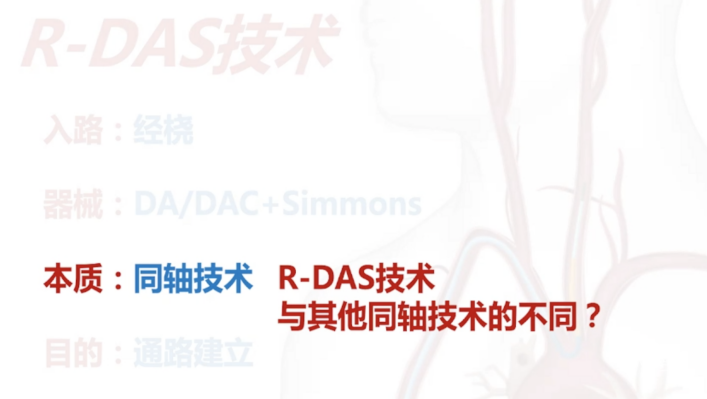

什么是R-DAS技术?

R-DAS技术,即经桡DA/DAC/DAS+Simmons导管同轴技术。应用于经桡入路,核心器械为远端通路导引导管(如通桥银蛇DA远端通路导引导管)或者中间导管、长鞘等这类头端相对柔软、高到位的导管+Sim造影导管(最常用的为Sim 2导管),本质是同轴技术,目的是为了实现经桡通路的建立。

R-DAS技术和其他同轴技术有何不同?

早期同轴技术的应用:在使用粗导管过弓时使用同轴技术来克服窗台效应,减少局部块脱落,增加导管通过的成功率。

过往的同轴技术是柔软内芯+相对支撑良好的外管,而R-DAS技术恰恰相反,是硬内芯(支撑)+软外管(建立通路)的组合。